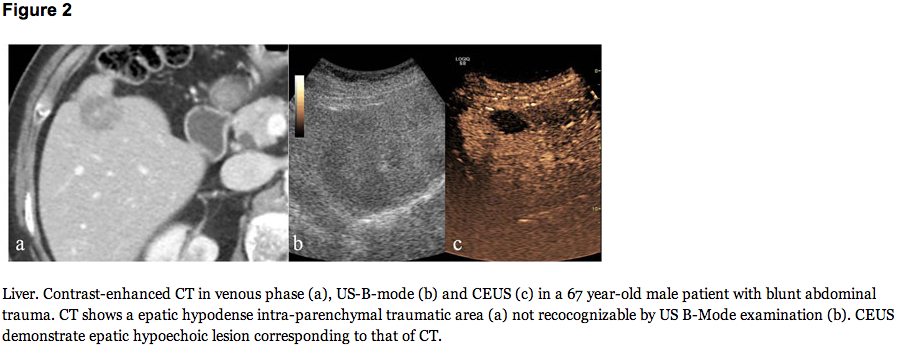

Here are some images from the authors in the article that makes the point: